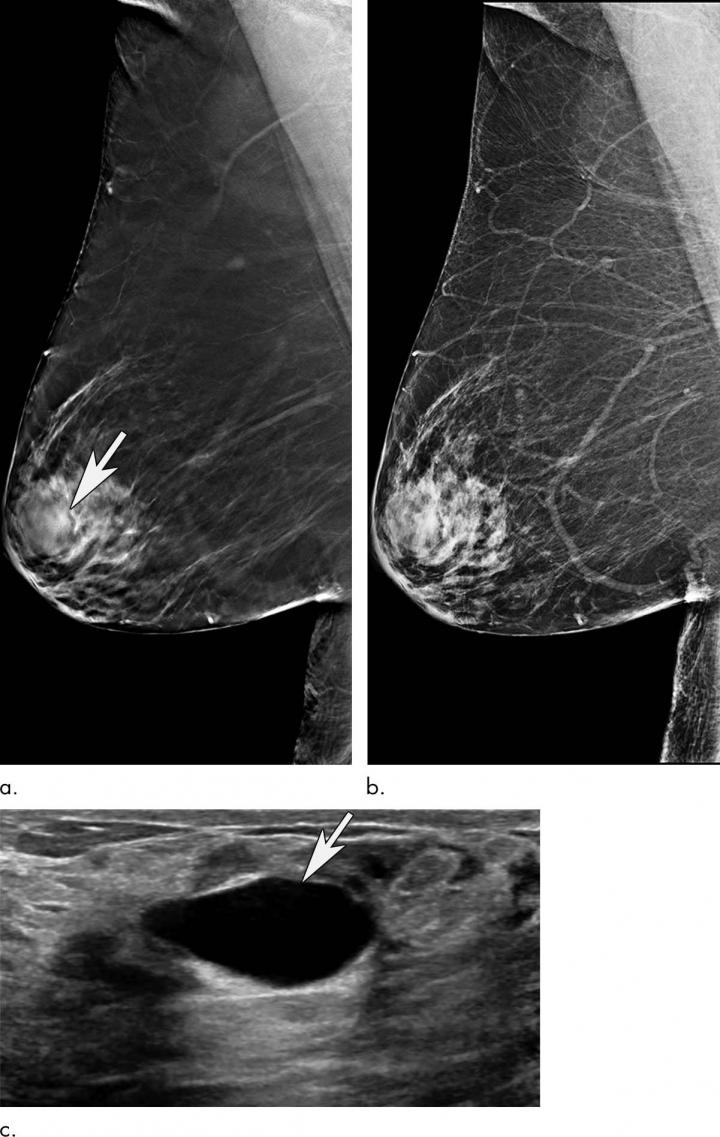

OAK BROOK, Ill. - Mammography remains an effective method for breast cancer screening in women ages 65 and older, with the addition of a 3-D technique called tomosynthesis improving screening performances even more, according to a study published in the journal Radiology .

Breast cancer is the most common cancer and the second most common cause of death from cancer among women in the United States. Research has shown that digital 2-D mammography (DM) is effective at reducing breast cancer-related mortality through early detection, when the cancer is most treatable. In 2011, the U.S. Food and Drug Administration approved tomosynthesis, also known as 3-D mammography, for breast cancer screening. Since then, it has become widely used as an adjunct to DM.

In the new study, researchers at Massachusetts General Hospital (MGH) sought to learn more about the performance of screening mammography in the older population and the added value of tomosynthesis. They compared screening mammograms from more than 15,000 women (mean age 72.7 years) who underwent DM with those of more than 20,000 women (mean age 72.1 years) who underwent tomosynthesis. Both approaches were highly effective at detecting cancer, but tomosynthesis had some advantages over the 2-D approach, including a reduction in false-positive examinations. Tomosynthesis also had a higher positive predictive value, the probability that women with a positive screening result will have breast cancer, and higher specificity, or the ability to distinguish cancer from benign findings, than DM.

"We've shown that screening mammography performs well in older women, with high cancer detection rates and low false-positives, and that tomosynthesis leads to even better performance than conventional 2-D mammography," said study lead author Manisha Bahl, M.D., M.P.H., radiologist at MGH and assistant professor of radiology at Harvard Medical School. "For example, the abnormal interpretation rate, which is the percentage of women who are called back for additional imaging after a screening mammogram, is lower with tomosynthesis than with conventional 2-D mammography. We also found that fewer cancers detected with tomosynthesis were lymph node-positive, suggesting that we are detecting cancers at an earlier stage. Detecting breast cancers at an early stage is the goal of screening mammography."

Dr. Bahl expects the combination of DM and tomosynthesis to eventually become the standard for screening at all practices.